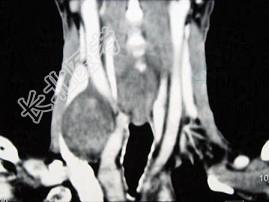

- 多项选择题男性,70岁, 右侧颈部无痛性肿块3个月,CT扫描如图所示, 请选择正确的描述和答案 ( )

A、右颈动脉间隙内见类圆形软组织肿块影,密度欠均匀,边缘光整

B、右侧颈静脉被推压至肿块外后方

C、右侧颈动脉被推压至肿块内后方

D、考虑迷走神经源性肿瘤

E、考虑交感神经源性肿瘤